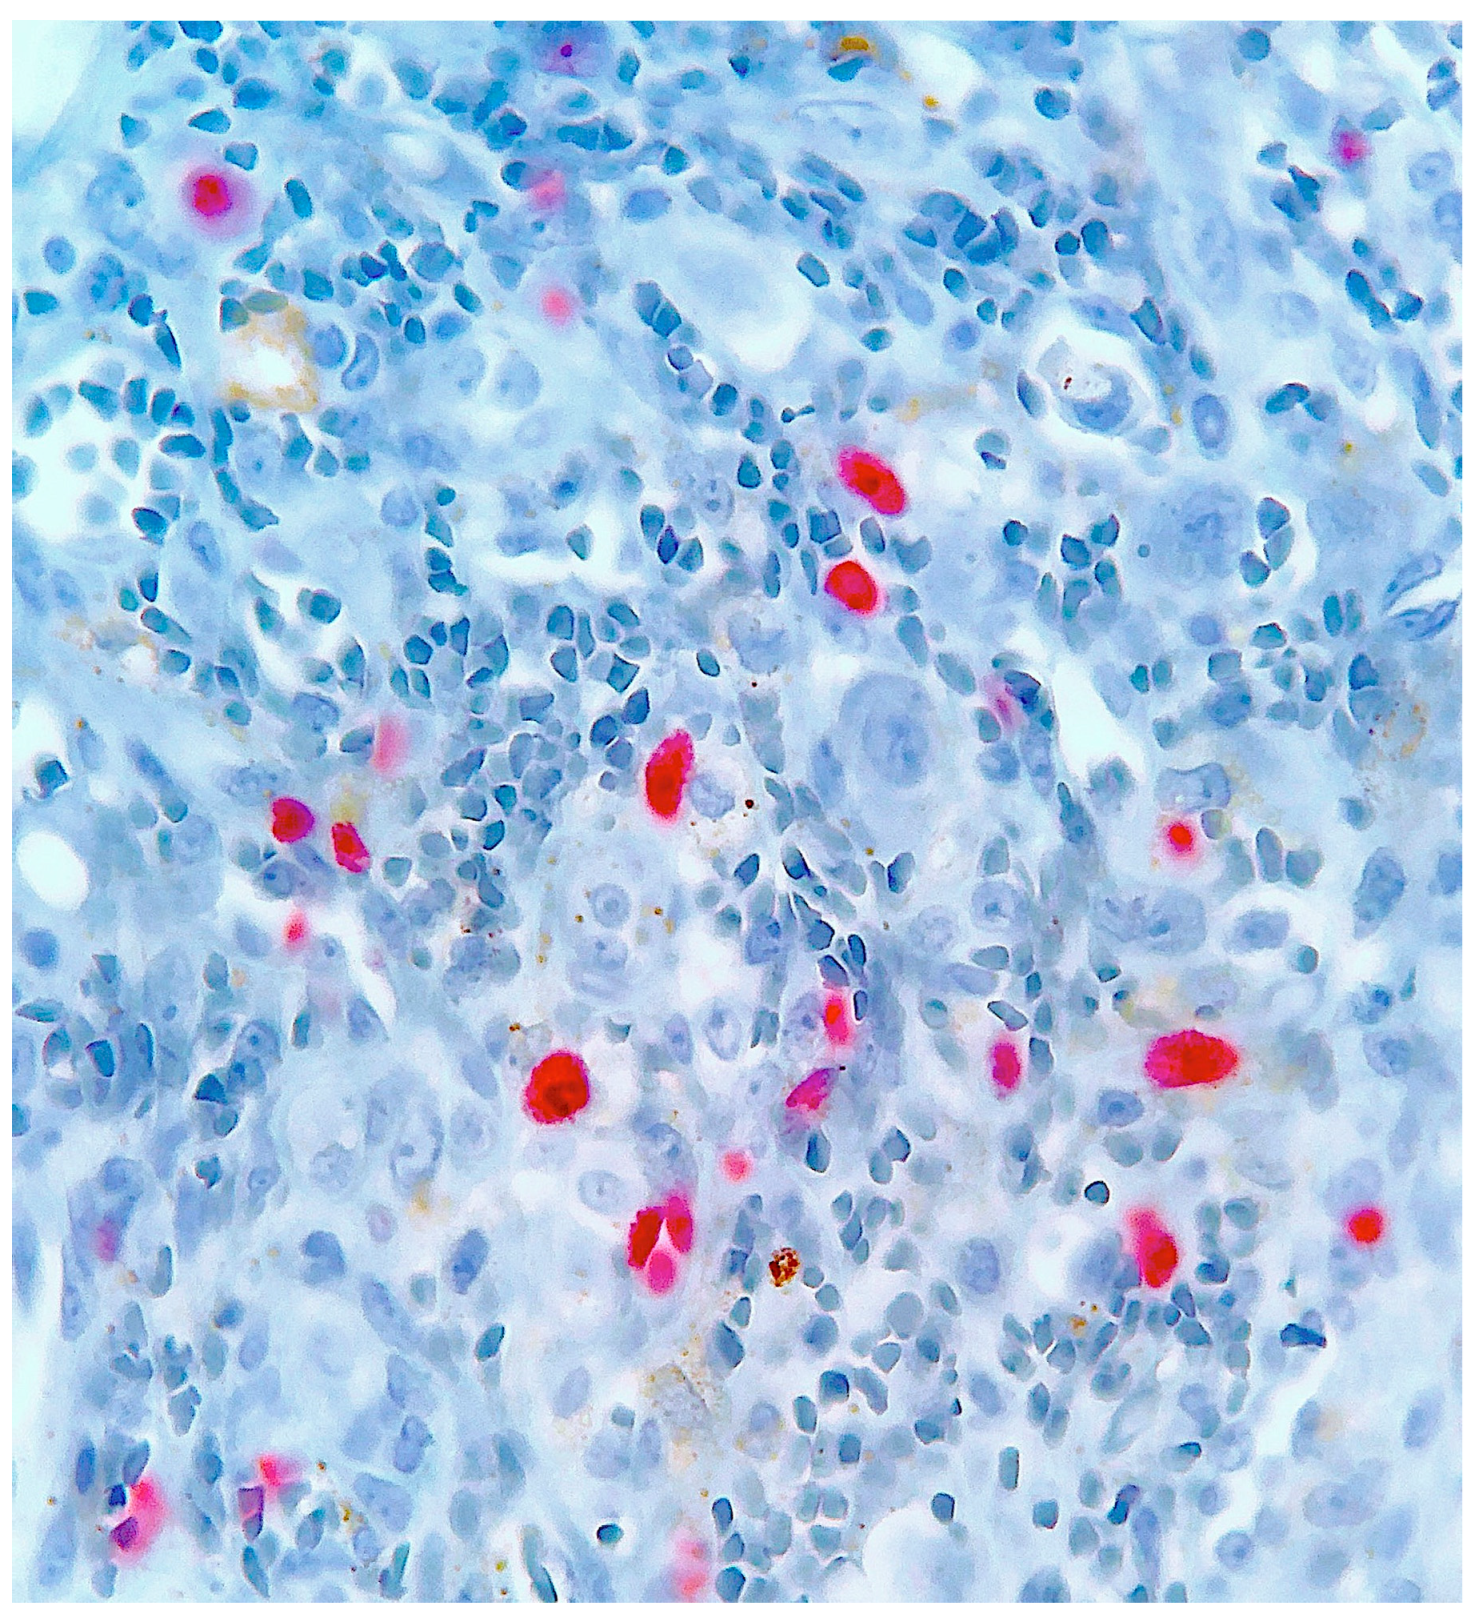

2. Case Report